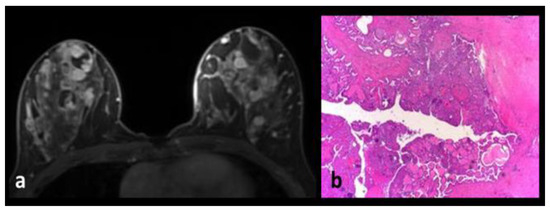

Juvenile Papillomatosis

Intraductal Papilloma-Intraductal Papillomatosis

Apocrine Metaplasia